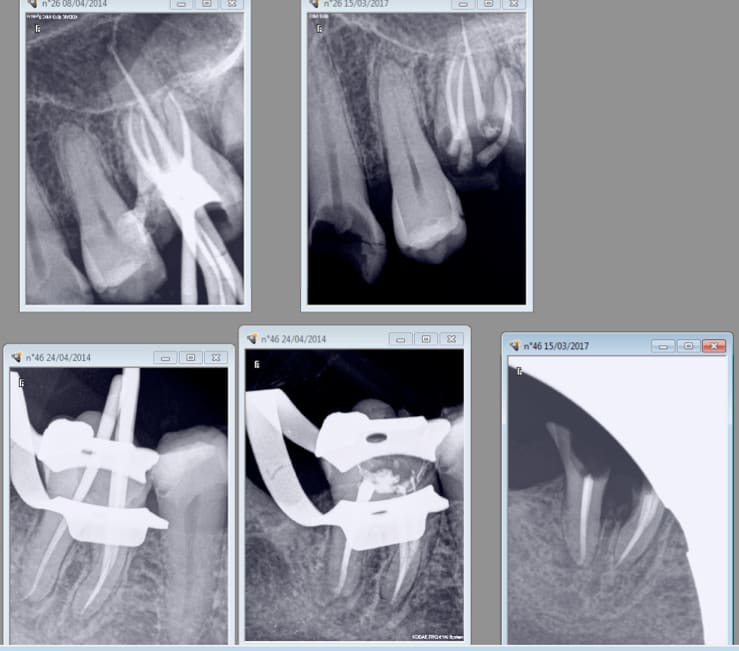

Patiente CMU n'a pas donné suite à ses soins ( qui étaient pourtant intégralement remboursés) en 2014. 2017 26, 37 , 47 à virer et elle consulte pour 11 cassée. -)

La pauvre elle n'a pas accès aux implants gratuits. -)))

C'est pas uniquement une question d'argent mais aussi une question de je m'en foutisme.